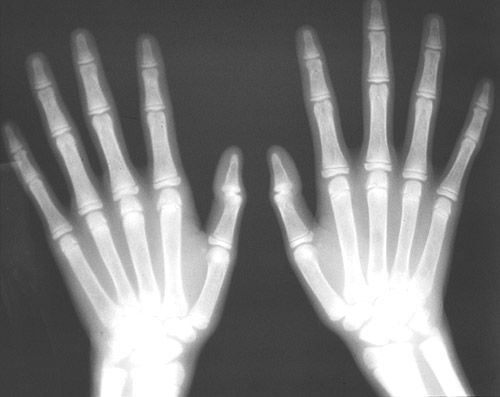

![]() | This radiograph of the hand demonstrates marked diffuse osteosclerosis, a manifestation of renal osteodystrophy in a patient with chronic renal failure and secondary hyperparathyroidism. The changes with secondary hyperparathyroidism include osteitis fibrosa cystica and osteopenia (similar to changes with primary hyperparathyroidism) but osteosclerosis may also occur. |